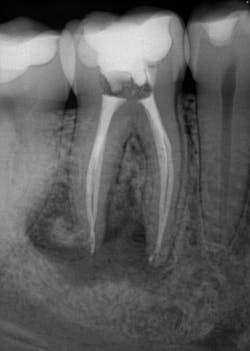

Various clinical presentations and risk factors can influence endodontic success or failure, including but not limited to the quality of the root canal performed and the seal of the coronal restoration.2 In addition to the aforementioned factors, the presence and size of a periapical lesion can directly affect the prognosis and treatment outcome. Classic literature highlights this shift in long-term success rates from 96% for vital/nonvital cases without the presence of a periapical lesion to 86% when a periapical lesion is present.3

Periapical radiographs have been commonly used to evaluate the size of periapical lesions. However, periapical radiographs have limitations, because the information is rendered in only two dimensions. A periapical lesion can only be detected in the radiograph when the mineral loss of bone reaches 30%–50%.4